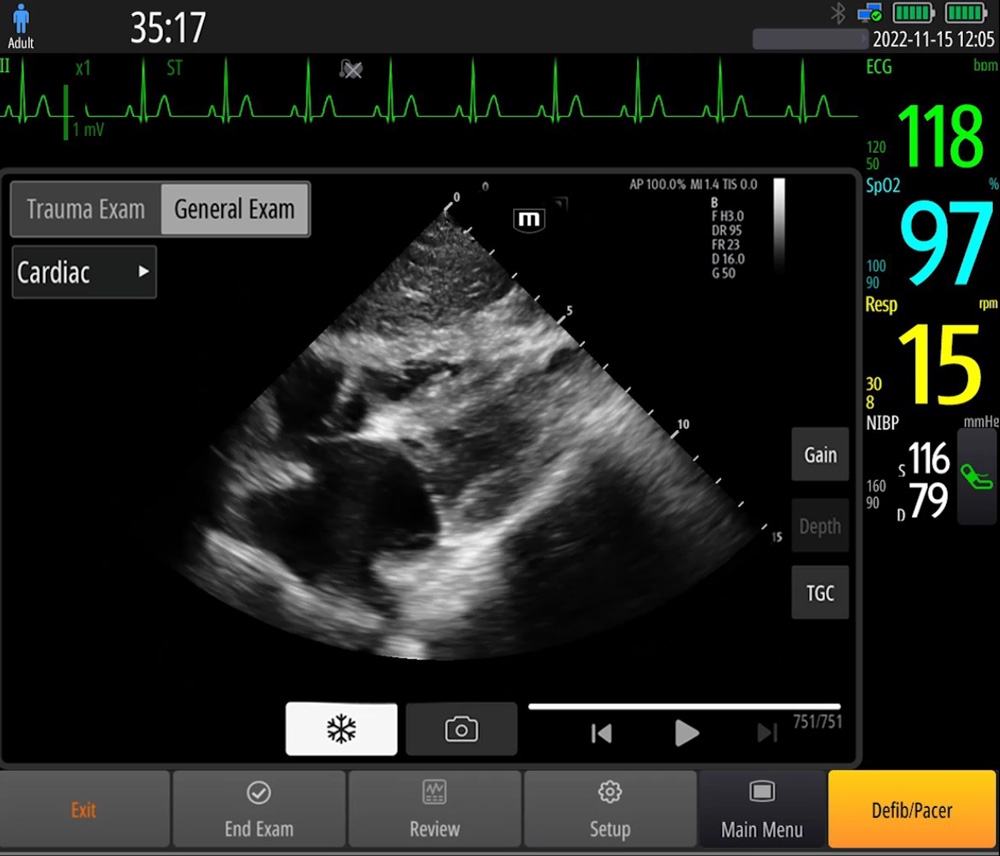

?chographie sur le lieu de soins (Point of Care ultrasound, POCUS)

Les fonctions ĂŠchographiques intĂŠgrĂŠes facilitent le diagnostic sur site et fournissent un guide dâutilisation intelligent pour une intuitivitĂŠ renforcĂŠe.

- RImages de rĂŠfĂŠrence & Guides dâutilisation

- Sonde phased array?: haute rĂŠsolution, largement utilisĂŠe